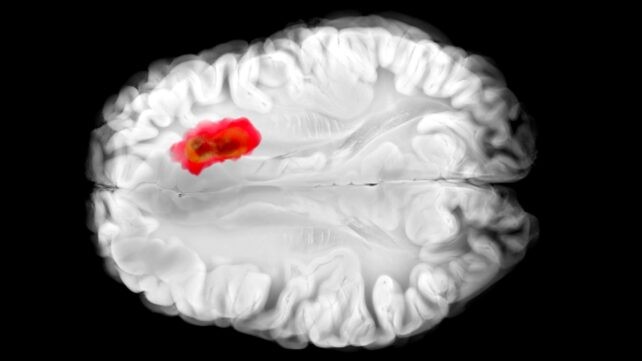

Hydralazin, ein seit Jahrzehnten verwendetes Vasodilatator zur Behandlung von Bluthochdruck, wirkt immer noch nicht vollständig geklärt. Eine neue Studie von der University of Pennsylvania beantwortet wichtige Fragen zu diesem Medikament – und legt eine faszinierende Verbindung zu einem der tödlichsten Hirntumore nahe. Die Forscher untersuchten die Wirkungen von Hydralazin an menschlichen und Mäusezellen und stellten fest, dass es das Enzym 2-Aminoethanethioldioxygenase (ADO) blockiert. Dieses Enzym gilt offenbar als Mitspieler bei aggressiven Glioblastom-Hirntumoren. Das neue Verständnis von Hydralazin könnte den Weg zu neuen Krebstherapien ebnen – und die Wirksamkeit des Medikaments für seine aktuellen Ziele verbessern. „Hydralazin ist eines der frühesten Vasodilatatoren, die jemals entwickelt wurden, und es ist immer noch eine Erstlinienbehandlung für Präeklampsie – eine hypertensive Erkrankung, die weltweit 5–15 Prozent der mütterlichen Todesfälle verursacht“, sagt Kyosuke Shishikura von der University of Pennsylvania. „Es stammt aus einer 'Pre-Target'-Ära der Arzneimittelentdeckung, in der Forscher sich darauf verließen, was sie in Patienten zuerst sahen, und erst später versuchten, die Biologie dahinter zu erklären.“ Die Forscher beschreiben ADO als eine „Alarmglocke“, die den Körper bei fallenden Sauerstoffwerten warnt. Sie löst eine Kaskade aus, indem sie sogenannte RGS-Proteine (Regulatoren des G-Protein-Signalwegs) zerstört. Frühere Studien haben gezeigt, dass Glioblastom-Tumoren oft hohe ADO-Werte aufweisen, die es ihnen ermöglichen, Hypotaurin zu produzieren, was das Ausbreiten der Krebszellen, ihr Überleben und ihre Stress-Toleranz erhöht. Vor dieser Studie gab es jedoch keine ADO-Inhibitoren. Hydralazin mutet ADO effektiv: RGS-Proteine werden nicht angegriffen, Blutgefäße werden nicht verengt, und der Blutdruck sinkt. In Experimenten mit menschlichen Glioblastomzellen stoppte Hydralazin das Tumorwachstum, indem es ADO blockierte. Es ist sehr früh – die Effekte von Hydralazin müssen in klinischen Studien an Menschen mit Glioblastom getestet werden – aber diese Ergebnisse sind vielversprechend und könnten Wege eröffnen, die Ausbreitung dieser notorisch schwer zu behandelnden Hirntumoren zu kontrollieren. Die neu entdeckte Mechanik erklärt auch, warum Hydralazin eine effektive Behandlung für Präeklampsie ist. Das bedeutet, das Medikament kann besser entwickelt und personalisiert werden, um Nebenwirkungen zu reduzieren und Ergebnisse zu verbessern. „Das Verständnis, wie Hydralazin auf molekularer Ebene wirkt, bietet einen Weg zu sichereren, selektiveren Behandlungen für Schwangerschaftsbedingte Hypertonie – potenziell bessere Ergebnisse für Patientinnen, die am größten Risiko tragen“, sagt die Chemikerin Megan Matthews von der University of Pennsylvania. „Es ist selten, dass ein altes Herz-Kreislauf-Medikament uns etwas Neues über das Gehirn lehrt“, sagt Matthews. „Aber genau das hoffen wir zu finden – ungewöhnliche Verbindungen, die neue Lösungen ermöglichen könnten.“ Die Forschung wurde in Science Advances veröffentlicht. Verwandt: Serotonin könnte eine unerwartete Rolle in Krebs spielen, Wissenschaftler entdecken.